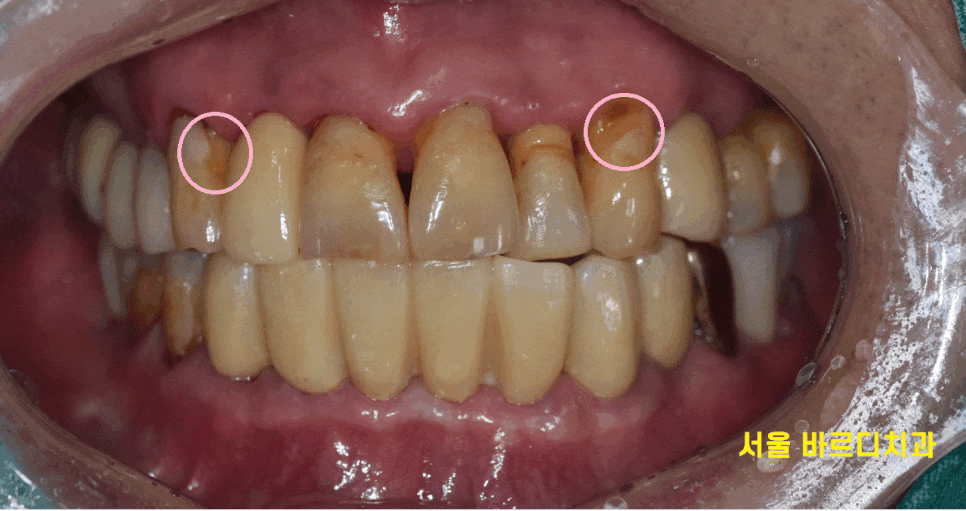

씹으면 오른쪽 왼쪽 다 아프고

염증이 있는거같아요

치아 불편감으로 저희 병원을 내원해주신 환자분입니다.

녹아버린 잇몸뼈로 치아가 흔들 흔들

길어 보이는 상황이었습니다.